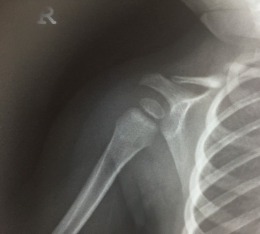

Συγγενής ψευδάρθρωση δεξιάς κλείδας

Κοριτσάκι έξι ετών με συγγενή ψευδάρθρωση δεξιάς κλείδας. Εξαιρετικό λειτουργικό αποτέλεσμα μετά από χειρουργική θεραπεία.